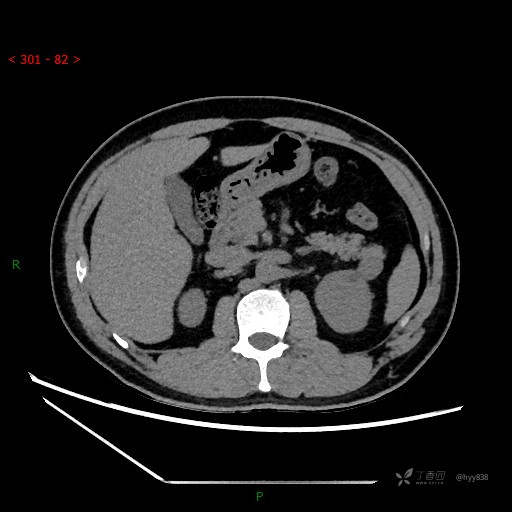

胰腺CT平扫